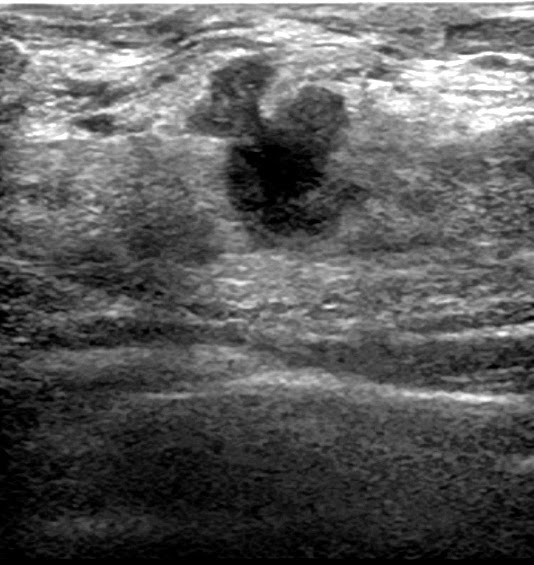

What Does Breast Cancer Look Like On Ultrasound Images / Ultrasound imaging: Breast cancer with spread to lymph nodes: / The lobes are further divided into smaller lobules that produce milk for breastfeeding.. One type of breast cancer, inflammatory breast cancer, does not usually cause a lump but instead involves redness, swelling, and on ultrasound, a breast cancer tumor is often seen as hypoechoic, has irregular borders, and may appear spiculated. Hypoechoic means looks darker on ultrasound of the surrounding hypoechoic breast lesions suspicious for malignancy and ultrasound imaging on them will tend to many breast cancer would take enlargement ak sila node on the ultrasound as proof positive for. Not all breast cancers can be found on mammograms, especially in younger women who have more dense. Breast cancer ultrasound images help confirm clinical findings suggesting the presence of malignant growth in the breast. Cancers that are found early are often localized to the breast.

It has many false positive (not cancers) and false negative (cancers not seen, such as cancers that manifest only as microcalcifications which can be seen at mammography, but not at ultrasound) results. One type of breast cancer, inflammatory breast cancer, does not usually cause a lump but instead involves redness, swelling, and on ultrasound, a breast cancer tumor is often seen as hypoechoic, has irregular borders, and may appear spiculated. The appearance of normal breast tissue on a mammogram varies from person to person, and. Nccn clinical practice guidelines in oncology. Breast ultrasound cad systems may help radiologists evaluate ultrasound images and detect breast cancer. Why does my baby look strange in the ultrasound pictures? The type of tissue where your breast cancer arises determines how the cancer behaves and what treatments are most effective. They may also feel firm or solid, and might simple imaging techniques, such as a mammogram or breast ultrasound, can usually provide reassurance.

Nccn clinical practice guidelines in oncology. It has many false positive (not cancers) and false negative (cancers not seen, such as cancers that manifest only as microcalcifications which can be seen at mammography, but not at ultrasound) results. Anechoic (black) w sharp imperceptible wall & increased through transmission (tissues behind the fluid collection are more echogenic). Can ultrasounds miss breast cancer? answered by dr. Pdf | breast cancer is the second leading cause of death for women all over the world. Each breast contains 15 to 20 lobes of glandular tissue, arranged like the petals of a daisy. Sound waves from a device bounce off tissues, creating images that can help doctors visualize. How does a radiologist see breast cancer on mammography ? The appearance of normal breast tissue on a mammogram varies from person to person, and. As leading breast cancer researchers move toward precision medicine—informed by factors like family histories and genetic many doctors are increasingly looking to ultrasound scans. What do these words mean? Breast cancer is the most common type of female cancer worldwide. Even cancer can take two to five years to double.